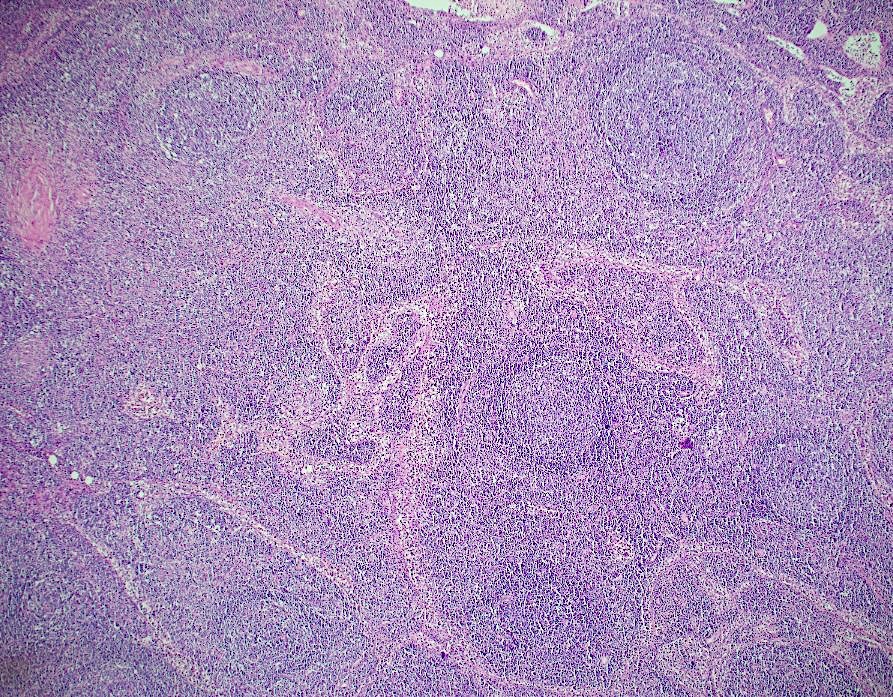

Tissue sections show a diffuse atypical lymphoid infiltrate that completely effaces the normal nodal architecture. The infiltrate is composed of numerous small lymphocytes with round to mildly irregular nuclei, clumped chromatin, inconspicuous nucleoli and scant cytoplasm. There are also expanded pale areas that contain intermediate sized cells with more open chromatin and distinct single to multiple nucleoli. These cells are most consistent with prolymphocytes/paraimmunoblasts and form the proliferation centers characteristic of CLL/SLL. Occasional centroblastic-type B-cells are noted within these proliferation centers. In addition, there are scattered single to multinucleated cells that have irregular nuclear membranes with pale, vesicular chromatin and prominent inclusion-like, eosinophilic nucleoli. These cells morphologically resemble Hodgkin cells, Reed-Sternberg cells, mummified forms and other variants. These large cells are more evident in areas with a histiocyte rich background and around foci of necrosis. Occasionally, apoptotic bodies and mitotic figures are seen.

The morphologic and immunophenotypic findings are consistent with involvement by the patient’s known small lymphocytic lymphoma/chronic lymphocytic leukemia (SLL/CLL) with aggressive morphological features. The aggressive features include expanded proliferation centers and an elevated Ki-67 proliferative index (40%). Additionally there are histiocyte/T-cell rich areas composed of multiple EBV positive large atypical cells with morphologic and immunophenotypic features compatible with Hodgkin/ Reed-Sternberg cells. These areas are most in keeping with evolving classic Hodgkin lymphoma. Sheets of large cells indicative of large cell transformation are not seen, although increased scattered large centroblastic-type B cells are present.

Lymph node involvement by CLL/SLL will typically show a diffuse proliferation of small lymphocytes with effacement of the normal nodal architecture. The small lymphocytes have round nuclei, clumped chromatin and scant cytoplasm. Scattered paler areas known as proliferation centers are characteristic of this entity. The proliferation centers are composed of a mixture of cell types including small lymphocytes, prolymphocytes and paraimmunoblasts. Prolymphocytes are small to medium in size with relatively clumped chromatin, whereas paraimmunoblasts are larger cells with round to oval nuclei, dispersed chromatin, eosinophilic nucleoli and slightly basophilic cytoplasm. Some cases show increased and enlarged proliferation centers with a higher proliferation rate. This must be distinguished from large cell transformation.1

Aggressive features of CLL/SLL include proliferation centers that are broader than a 20x field or becoming confluent. An increased Ki-67 proliferation >40% or >2.4 mitoses in the proliferation centers can also portend a more aggressive course. These cases tend to have worse outcomes than typical CLL/SLL and better outcomes than cases that have undergone Richter transformation to diffuse large B-cell lymphoma (DLBCL). Transformation to DLBCL occurs in 2-8% of patients with CLL/SLL. Less than 1% of patients with CLL/SLL develop classic Hodgkin lymphoma (CHL). In order to diagnose CHL in the setting of CLL/SLL, classic Reed-Sternberg cells need to be found in a background appropriate for CHL, which includes a mixed inflammatory background. The majority of these CHL cases will be positive for EBV.1